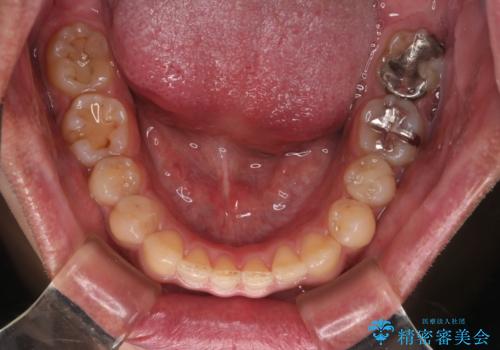

【モニター】インビザライン 前歯の捻れを治したい

- 30代男性

- 矯正装置

- インビザライン

- 治療期間

- 1年6ヶ月

- 治療計画

- 上下の前歯のがたつきを主訴に来院されました。インビザラインで治療可能と判断致しましたので、IPR(歯と歯の間を削る処置)と歯列弓拡大をして

がたつきをとる治療計画を立てました。

マウスピースをしっかり使用していただいたことで、主訴である前歯のがたつきも改善され

リファイメントも1回のみで治療を終了することが出来ました。